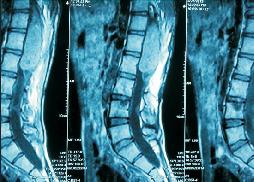

Percutaneous Spinal Fixation